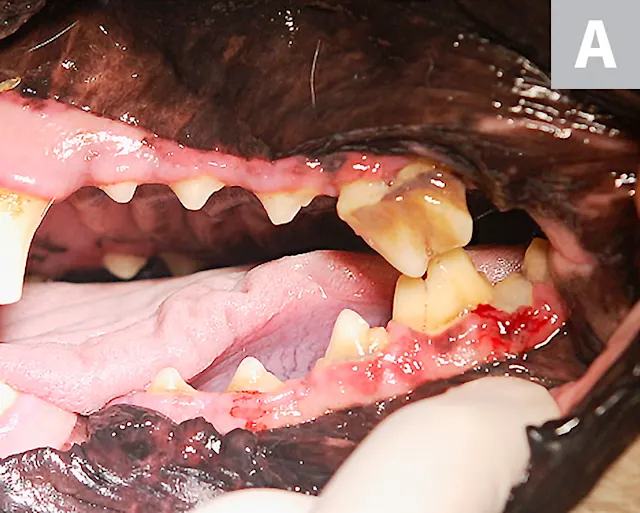

FIGURE 2A

Intraoral image (A) and close-up view (B) of the left maxillary fourth premolar showing signs of advanced periodontal disease. Gingivitis, gingival recession, furcation involvement of the left maxillary fourth premolar, and gingivitis of the third and fourth mandibular premolars and the first mandibular molar can be seen.